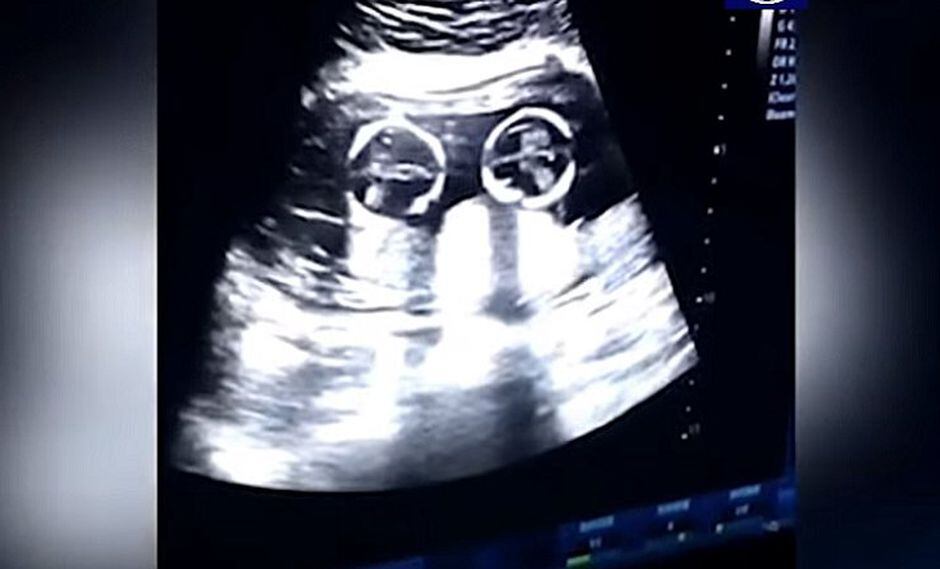

Un curioso video se ha viralizado en las redes sociales. En ella se puede ver lo que sería la "pelea" de unas gemelas dentro del útero de su madre.

El video fue captado durante la visita de rutina de la madre al doctor a los cuatro meses de gestación.

En las imágenes que circula en las redes parecería que las bebés están discutiendo, mientras su padre las graba desde el exterior.

Las gemelas fueron llamas Cherry y Strawberry y el video compartido ha sido reproducido más de 2,5 millones de veces.